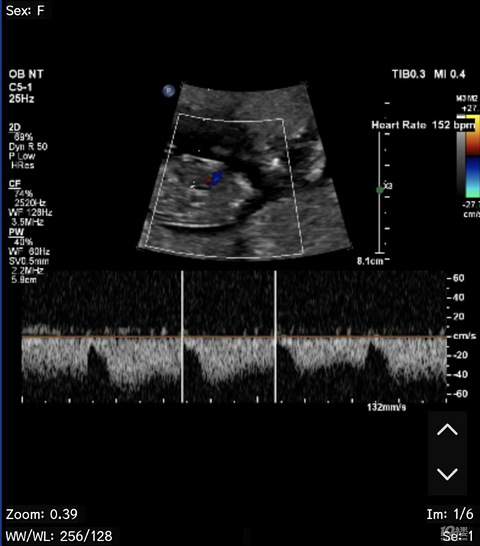

预产期:2024年9月15日 建卡医院:椒江妇幼保健院 产检医院:椒江妇幼保健院,台州妇女儿童医院 宝宝小名:小团子 生产医院:台州妇女儿童医院 B超照片: